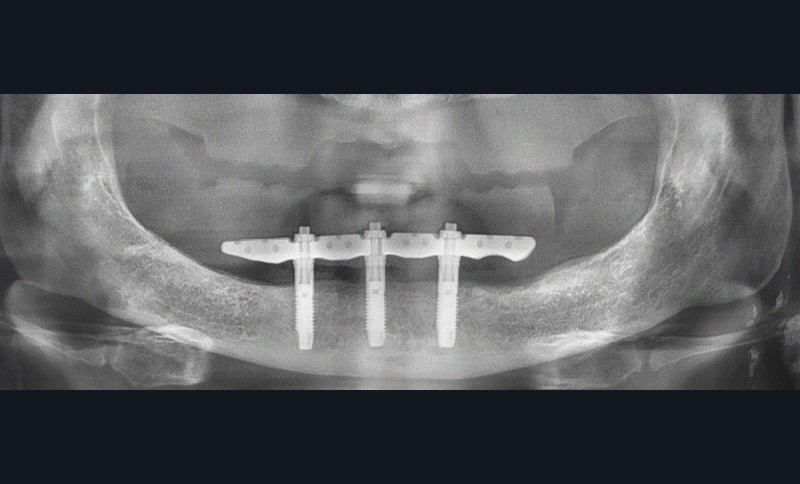

Le patient, édenté total, souhaite une réhabilitation maxillomandibulaire avec une forte demande de fixité pour sa prothèse inférieure. La topographie symphysaire [2], validée par un cliché numérique, nous ouvre l’opportunité d’une mise en charge immédiate d’un bridge sur pilotis type Trefoil, confirmée ultérieurement par le montage directeur (fig. 1) [3].

La planification virtuelle implantaire s’ensuit. Une fois encore, le numérique conforte ses atouts. Les matchings, sous réserve d’une parfaite correspondance, offrent une multitude d’informations optimisant la parfaite concordance entre anatomie osseuse, implants (3 CC RP 5×11,5mm), barre Trefoil et montage directeur (fig. 3). Cette somme d’informations permet alors de visualiser la barre Trefoil au travers du montage directeur.

L’occlusion et les accès prophylactiques sont de nouveau contrôlés. S’ensuivent les séquences de maintenance classiques. Un contrôle radiographique (fig. 8) ainsi qu’une surveillance annuelle sont mis en place.